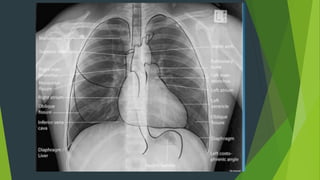

Giải phẫu hệ hô hấp

Tác dụng của phim X quang phổi nghiêng?

 Xác định vị trí của tổn thương theo thùy và phân thùy

 Chẩn đoán định hướng các khối u trung thất

 Khảo sát các vùng sau tim trái, sau vòm hoành hoặc trước rốn

phổi

 Chẩn đoán TDMP ít mà dịch khu trú ở góc sườn hoành sau không

nhìn rõ trên phim chụp thẳng